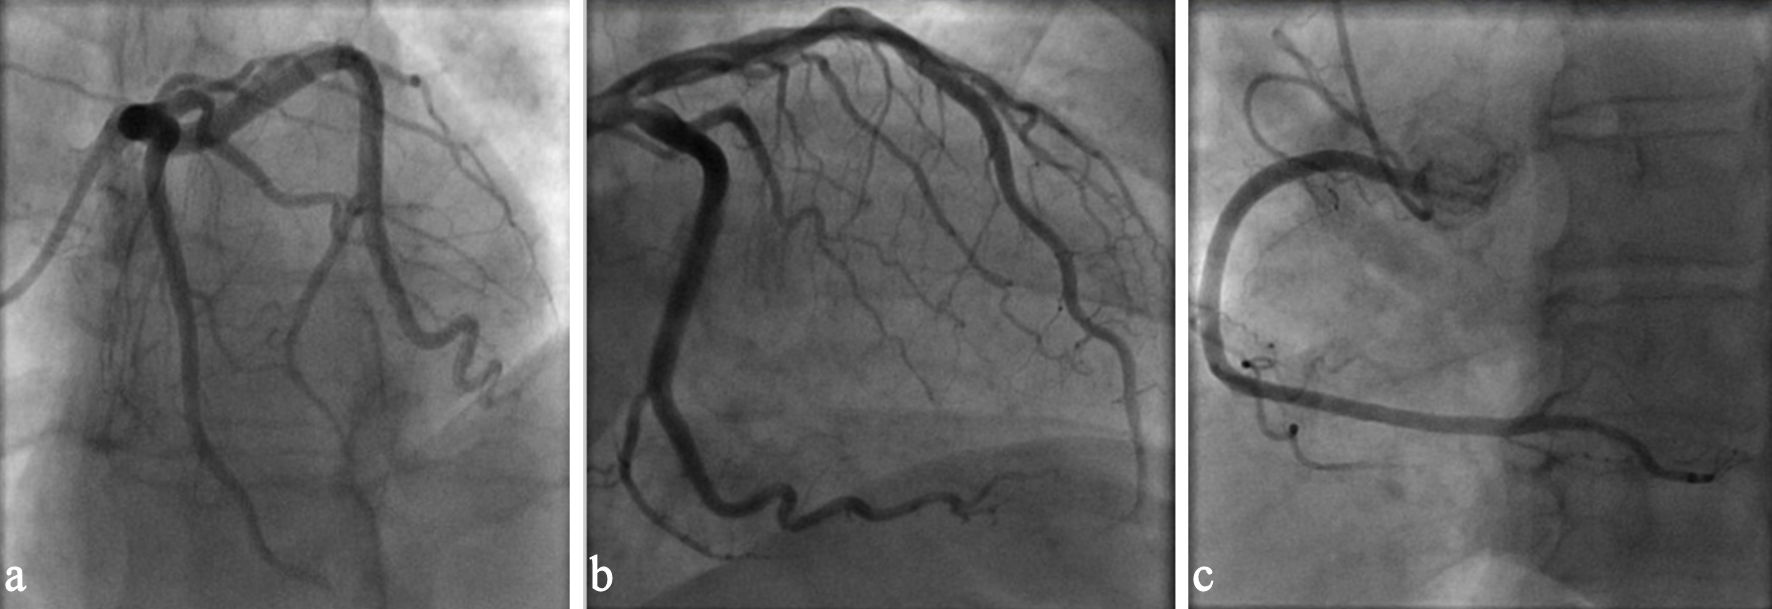

She underwent cardiac catheterization during her hospital stay, which ruled out obstructive coronary artery disease as etiology for the presence of systolic dysfunction (Fig. 3). A transesophageal echocardiogram performed prior to a successful direct-current cardioversion revealed mild left atrial enlargement, excluded the presence of thrombi in left atrium, and confirmed a severely decreased ventricular ejection fraction. A cardiac magnetic resonance imaging (CMR) was not pursued, as the patient declined the study due to associated risks related to her kidney dysfunction. During her hospital course, she was treated with intravenous (IV) loop diuretics and was placed on rivaroxaban (CHA2DS2-VASc score of 3, female gender, hypertension (HTN), CHF). A beta-blocker, angiotensin receptor-neprilysin inhibitor (ARNI), and sodium-glucose cotransporter 2 (SGLT2) inhibitor were started as part of management for heart failure with reduced ejection fraction. Mineralocorticoid receptor antagonist was not started due to impaired renal function and borderline hyperkalemia. She was discharged clinically stable and symptomatically improved and is being followed as an outpatient for titration of guideline-directed medical therapy for heart failure with reduced ejection fraction.

Click for large image

Figure 3. (a) Coronary angiography left anterior oblique view demonstrating patent left main and left anterior descending coronary arteries. (b) Coronary angiography showing unobstructed left circumflex coronary artery. (c) Coronary angiography right anterior oblique view demonstrating patent right coronary artery.